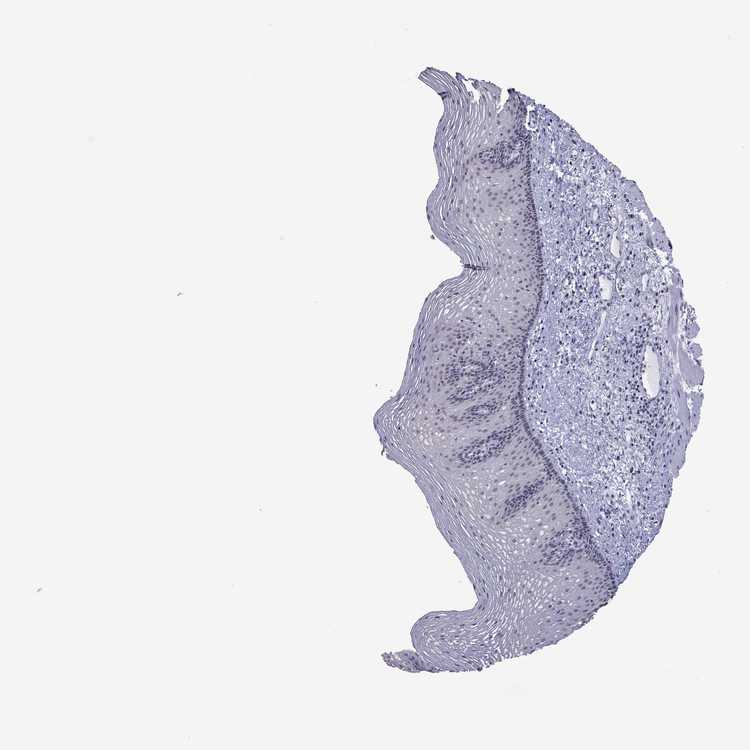

TISSUE PRIMARY DATA ESOPHAGUS Show tissue menu

Esophagus

ESOPHAGUS - Antibody stainingi

Antibody staining in the annotated cell types in the current human tissue is reported as not detected, low, medium, or high, based on conventional immunohistochemistry profiling in selected tissues. This score is based on the combination of the staining intensity and fraction of stained cells.

Each image is clickable and will lead to virtual microscopy that enables deeper exploration of all samples and also displays staining intensity scores, fraction scores and subcellular localization as well as patient and tissue information for each sample.

Antibody HPA070440Antibody HPA073138

Squamous epithelial cells Not detectedNot detected